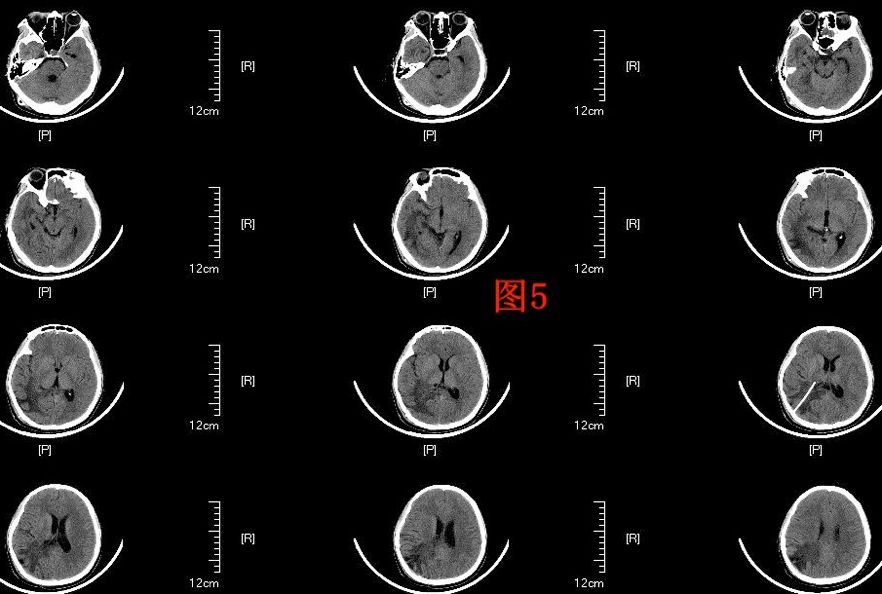

患者于术后第64天再次入院,入院后行头部MRI(图4)检查提示右侧侧脑室颞角、后角扩张并周围脑组织水肿、中线明显移位,并行腰穿测压为280cmH2O,诊断为右侧侧脑室三角区脑膜瘤切除术后孤立颞角综合征,遂于术后第68天行侧脑室颞角腹腔分流术,分流管为美敦力可调压力分流管,术中设定压力范围为105~125mmH2O,术后复查头部CT以及MRI(图5、6)。

图5. 显示V-P分流术后复查头部CT。